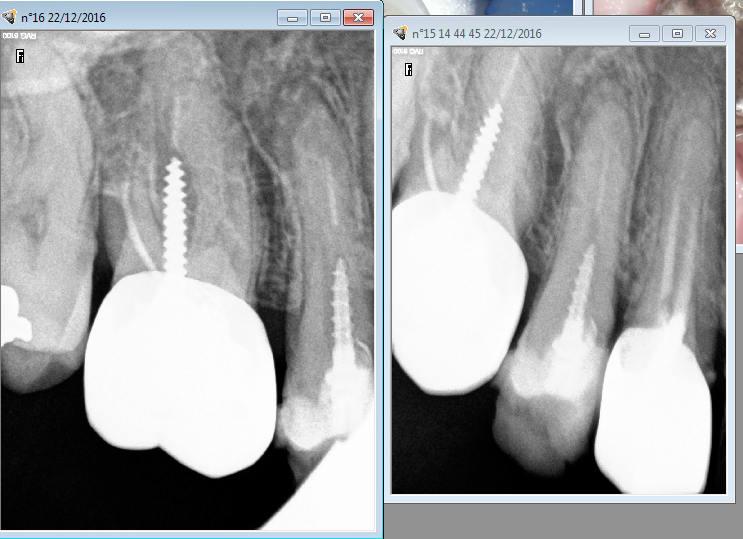

> Patient vu en urgence ( première fois) le 22/12 sur 15. ATB. je fais l'endo de

> 37 le 11 01 car j'avais le temps et remis le RTE de 15 la semaine suivante.

> Ben figurez vous qu'il a pris rendez vous ailleurs ( sans annuler les RDV au

> cabinet) au motif que j'ai laissé l'infection sur 15 et qu'on ne prend rendez

> vous chez le dentiste que quand on a mal au dents et la 37 ne faisait pas mal (

> la 15 non plus du reste après les ATB).

> Mon pauvre garçon si tu savais En plus de la 15 tu as des traitements

> magnifiques sur 16 et 14. -)

En principe c'est la 15 qui est à l'origine de la douleur ( sensibilité percussion). Il faut dire qu'étant donné la qualité des tt initiaux de 16,15,14 on a que l'embarras du choix. -)